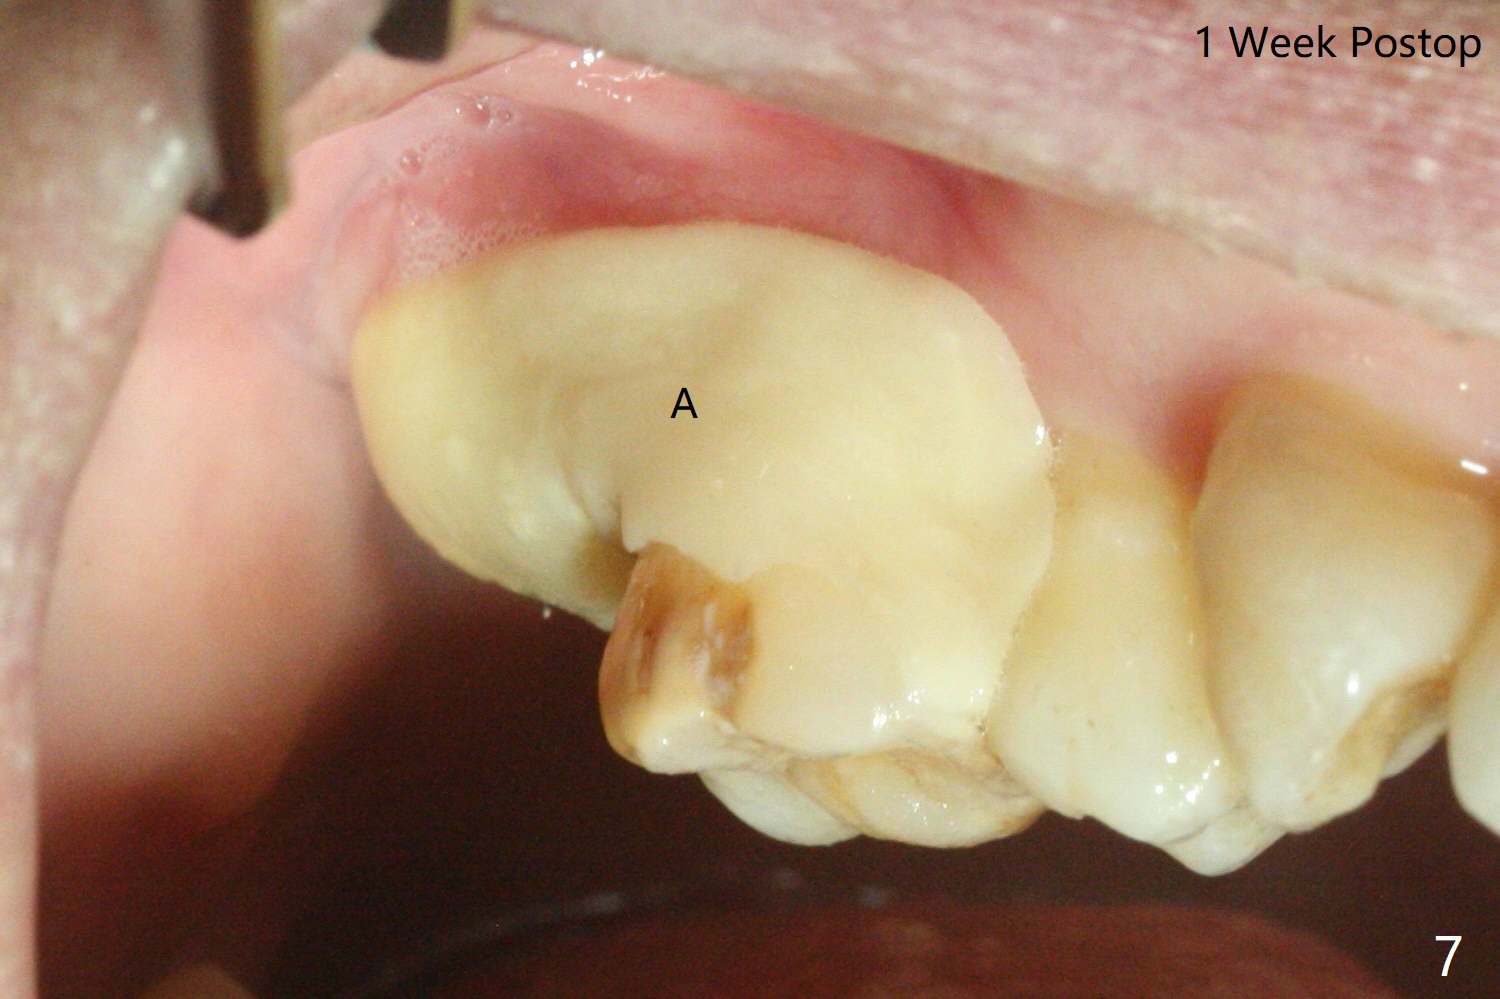

45岁女右上7严重骨质吸收,位点保存4-5个月,骨质高度增加,但是密度好像下降,准备上颌窦内提,同期种植,如果扭力太低,使用愈合帽,关闭伤口,最简易方法是利用环形刀保留牙龈。首先利用导板和导板环形刀(图一:好像绞肉机)在牙龈表面轻轻做一个标记(用手顺着金属圈按一下),然后取出导板,徒手使用锐利活检环形刀(图二),取出圆形牙龈,放入PRF上清液备用(图三)。接着放回导板完成提升(图四:*),不幸的是大一号正式植体无法取得稳定性,不得不取出,再大一号报废植体也无能取得固定,只好植骨(图五:*),放回保留的牙龈(图六:*),使用牙周胶水和树脂敷料固定。其实植骨前发现窦膜破裂,不过术后没有上颌窦并发症(术后服用激素)。术后7天树脂敷料稳定,局部卫生尚可(图七),准备术后一个月撤除敷料。